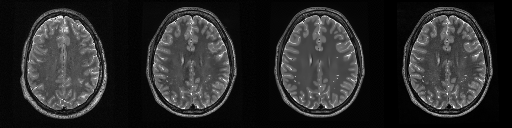

HCP T2w dataset

We utilize images from the publicly available Human Connectome Project (HCP) [51] T2-weighted (T2w) images dataset for the task of compressed sensing, which contains brain images from 47 patients. The HCP dataset includes cross-sectional images of the brain taken at different levels and angles.

Compressed sensing

We train a flow-based model from scratch on 10,000 randomly sampled images, utilizing the ncsnpp architecture [9] with minor adaptations for grayscale images. We employ compression rates , meaning . The measurement operator is given by a subsampled Fourier matrix, whose sign patterns are randomly selected. We evaluate our reconstruction algorithm’s performance on 200 randomly sampled test images.

We present the quantitative and qualitative results of compressed sensing in Tab. 1 and Fig. 4, respectively. As shown in Tab. 1, our method consistently achieves the best performance across varying compression rates . In Fig. 4, our method produces reconstructions that are more faithful to the original images, with fewer artifacts, leading to higher accuracy and clearer details.